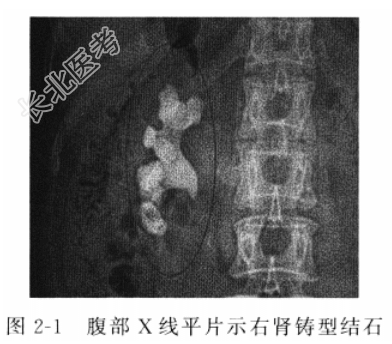

辅助检查 B超检查示右肾结石并右肾局限性积水声像;腹部X线平片(KUB)示右肾局部呈现高密度钙化影,呈铸型,纵径4.8cm,横径1.9cm(图2-1);尿液常规未见红细胞、白细胞、脓细胞,大便隐血试验(+)。